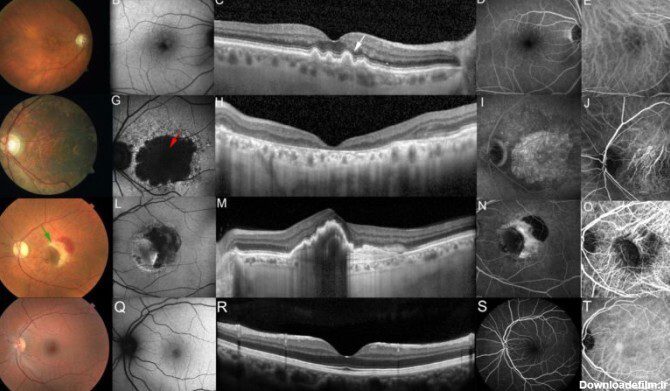

وی گفت: رتینیت پیگمنتوزا (RP)، نوعی از انحطاط شبکیه و یکی از رایجترین اشکال نابینایی ارثی است که شیوع آن در حدود یک در دو هزار و ۵۰۰ تولد است و با دژنراسیون پیشرونده شبکیه تشخیص داده میشود و منجر به نابینایی در شب و نهایتا نابینایی کامل میشود. شیوع بالا و این واقعیت که جوانان بیشترین گروه متاثر از این بیماری هستند، نه تنها بر سلامت عمومی، بلکه از دیدگاه اجتماعی و اقتصادی نیز تاثیر منفی دارد.

به گفته وی در این طرح که با هدایت سینا مظفری، عضو هیئت علمی دانشگاه علوم پزشکی مشهد و با همکاری مرکز تحقیقات چشم پزشکی دانشگاه علوم پزشکی شهید بهشتی اجرا شده، جهت افزایش انتقال ویروس در لایههای مختلف شبکیه در هنگام تزریق داخل زجاجیه که نوعی تزریق کمترتهاجمی است، جهشهایی در سطح پوشش ویروسی ایجاد شد. این جهشها به نفوذ بیشتر ویروس به تمام لایههای شبکیه کمک میکند. پس از تزریق ویروس تولید شده به درون چشم بیمار، ژن RPGR در گیرندههای نوری بیان میشود و از تخریب سلولهای شبکیه جلوگیری میکند.

حقشناس تصریح کرد: ویروسهای حاصل از این اختراع در یک مطالعه پیش بالینی به چشم موشهای یک ماهه تزریق شد و کارایی این ویروسها در انتقال ژن RPGR و نفوذ آنها از محل تزریق یعنی زجاجیه به جایگاه گیرندههای نوری در شبکیه و بیان اختصاصی RPGR در این سلولها به اثبات رسید.

به گفته این پژوهشگر در حال حاضر در دنیا ویروسهای AAV حامل ژن RPGR مورد استفاده در ژن درمانی بیماری رتینیت پیگمنتوزا وابسته به X بیشتر از نوع ۵ و ۸ است که برای تزریق از نوع زیرشبکیه مناسب است. در این اختراع برای اولین بار یک ویروس جدید AAV سروتیپ ۲ با نام AAV۲/۲.p (penta) YF/TV.GRK۱.coRPGRORF۱۵ ساخته شد که دارای جهشهای بیشتری در ژن کپسید است و این امر موجب افزایش پایداری و نفوذپذیری بالاتر ویروس میشود؛ بنابراین امکان تزریق مستقیم به درون زجاجیه چشم (به جای ناحیه زیرشبکیه) را به طور بسیار موثر و کارآمدی فراهم میکند و دیگر نیازی به تزریقهای بسیار تهاجمی زیرشبکیه که موجب التهاب شدید و همچنین جداشدگی شبکیه شده و در بیماران RP میتواند خطرناک باشد، نیست.